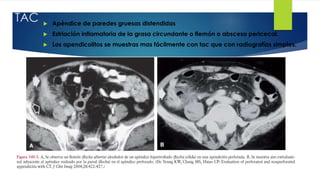

TAC  Apéndice de paredes gruesas distendidas

 Estriación inflamatoria de la grasa circundante o flemón o absceso pericecal.

 Los apendicolitos se muestras mas fácilmente con tac que con radiografías simples.

TAC  Apéndicede paredes gruesas distendidas  Estriación inflamatoria de la grasa circundante o flemón o absceso pericecal.  Los apendicolitos se muestras mas fácilmente con tac que con radiografías simples.